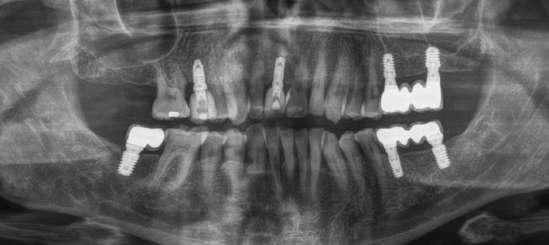

Presentamos el caso de un paciente masculino de 61 años de edad, bruxista, con evidentes desgastes en toda la dentición y cracks de esmalte que pueden observarse en las fotografías iniciales de la primera visita (figuras 1 y 2). En las fotografías

Figuras 1 y 2. Imágenes intraorales de la primera visita donde se hacen evidentes diferentes desgastes en los dientes anteriores y a mayor detalle crakcs en el esmalte, así como lesiones por abfracción en los cuellos de los dientes de los premolares y caninos superiores.

caso clínicoIMPLANTOLOGÍA

laterales se ponen de manifiesto aún más varias lesiones de esmalte que indican la parafunción en el paciente, unido a los desgastes excesivos en varias zonas (figuras 3 y 4). El paciente acude por dolor y movilidad en la pieza 11, que se ha incrementado en los últimos días, además de sensación de “diente crecido” que como podemos ver en las fotografías iniciales es real, ya que el diente se encuentra ligeramente extruido en relación con el contralateral. Estos signos parecen indicarnos una fractura o fisura. En la fotografía oclusal, podemos observar el desplazamiento del diente debido a la movilidad (figura 5). Posteriormente se realiza un sondaje positivo de la pieza, que lleva a 11 mm por lo que se confirma la sospecha de fractura y se procede a la exodoncia del diente, realizándose una regeneración posterior del alveolo con PRGF-Endoret y

esperándose 4 semanas hasta el cierre de los tejidos blandos y la neoformación ósea inicial para la colocación de un implante temprano. Cuatro semanas después, realizamos un cone-beam de control para conocer el estado del tejido óseo y poder planificar el implante. En el corte seccional observamos que se ha regenerado por completo el lecho receptor y tenemos un hueso óptimo para la inserción del implante, que por el tiempo transcurrido además es muy sencillo de expandir, con el propio implante generándose una expansión atraumática que nos permitirá ganar anchura ósea y con un implante estrecho de 3,5 mm de diámetro logramos posicionarlo sin dañar la desembocadura del nervio incisivo (figura 6). En cuanto a la longitud, con 7,5 es suficiente, no necesitándose un tamaño mayor para un correcto rendimiento biomecánico posterior.

Figuras 3 y 4. Fotografías laterales donde se evidencian los cracks de esmalte en varios dientes y los desgastes excesivos en varios puntos. En estas imágenes se hacen más evidentes las lesiones por abfracción.

Figura 5. Toma oclusal donde se hace evidente el desplazamiento del diente por el que consulta el paciente, que parece indicarnos una gran pérdida ósea a ese nivel.

Figura 6. Corte seccional de planificación del implante donde observamos el volumen óseo regenerado y la disposición del implante que se va a insertar por delante de la desembocadura del nervio incisivo.

Colocamos el implante generándose una ligera expansión vestibular, como mostramos en las imágenes intraoperatorias, para posteriormente ser sobrecorregido con hueso autólogo obtenido del fresado, embebido en PRGF-endoret y lograr una mayor anchura vestíbulo-lingual en la zona de colocación del im-

plante, clave para lograr una mejor estética y además un mantenimiento de los tejidos periimplantarios a largo plazo. En la fase quirúrgica colocamos además el transepitelial unitario para la realización de la carga inmediata y la colcación de un provisional atornillado horas después de la cirugía (figuras 7-14).

Figuras 7 y 8. Perforación inicial y colocación del implante expandiendo la zona vestibular.

Figuras 9 y 10. Visión vestibular tras la inserción del implante y colocación del transepitelial unitario para comenzar la carga inmediata.

Figuras 11 y 12. Sobre-corrección vestibular y cierre primario de los tejidos con un monofilamento no reabsorbible alrededor de la tapa de protección del transepitelial.

El paciente continúa en seguimiento posterior, con revisiones cada 6 meses durante los dos primeros años. En todas ellas no existe complicación ni pérdida ósea asociada al implante, tal como podemos ver en la radiografía de control a los dos años (figura 18).

Figura 14. Radiografía tras la colocación de la prótesis provisional de carga inmediata.

Figura 17. Radiografía tras la colocación de la prótesis definitiva.

Figura 18. Radiografía de control a los dos años, donde observamos el implante y la estabilidad del tratamiento.

Cinco años después, llevamos a cabo un nuevo cone-beam y en el podemos observar la evolución del implante y de la sobre-corrección vestibular llevada a cabo en la cirugía inicial. Tanto el implante como el hueso que se ha formado a nivel vestibular fruto del injerto empleado está estable y se mantiene sin pérdida ósea asociada, tal como mostramos en los cortes del cone-beam

inicial y final a los 5 años de seguimiento (figura 19). En las imágenes intraorales tomadas en este punto del seguimiento se constata el éxito del tratamiento (figuras 20 y 21). En la radiografía periapical, observamos con mayor detalle la regeneración del tejido óseo del diente en posición 11 así como la estabilidad ósea del implante (figuras 22 y 23).

Figura 19. Imagen inicial del cone-beam y final con el implante cargado a los 5 años de seguimiento con la estabilidad del implante y del hueso generado mediante el injerto

Figuras 22 y 23. Radiografía periapical inicial y a los 5 años de seguimiento.